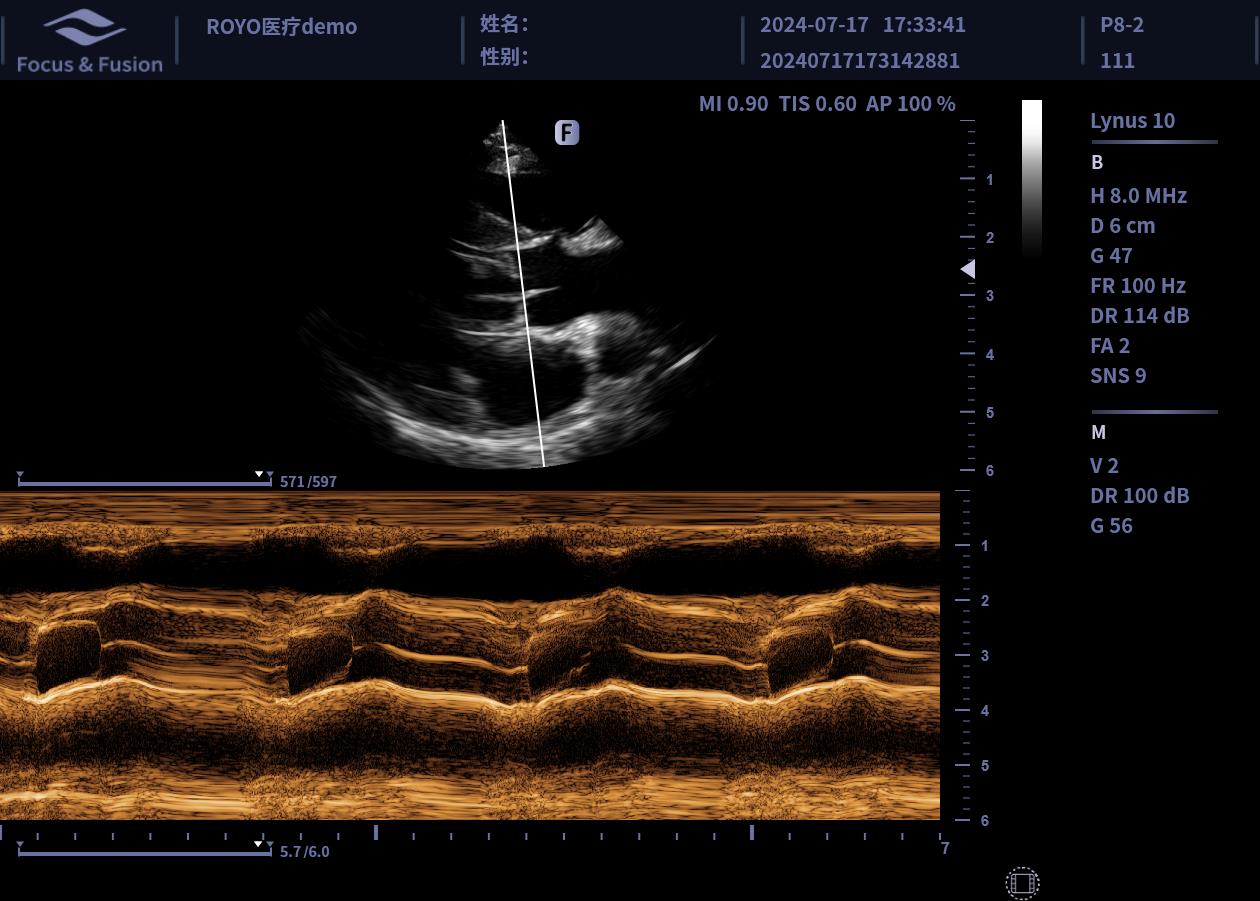

圖片展示

Image List